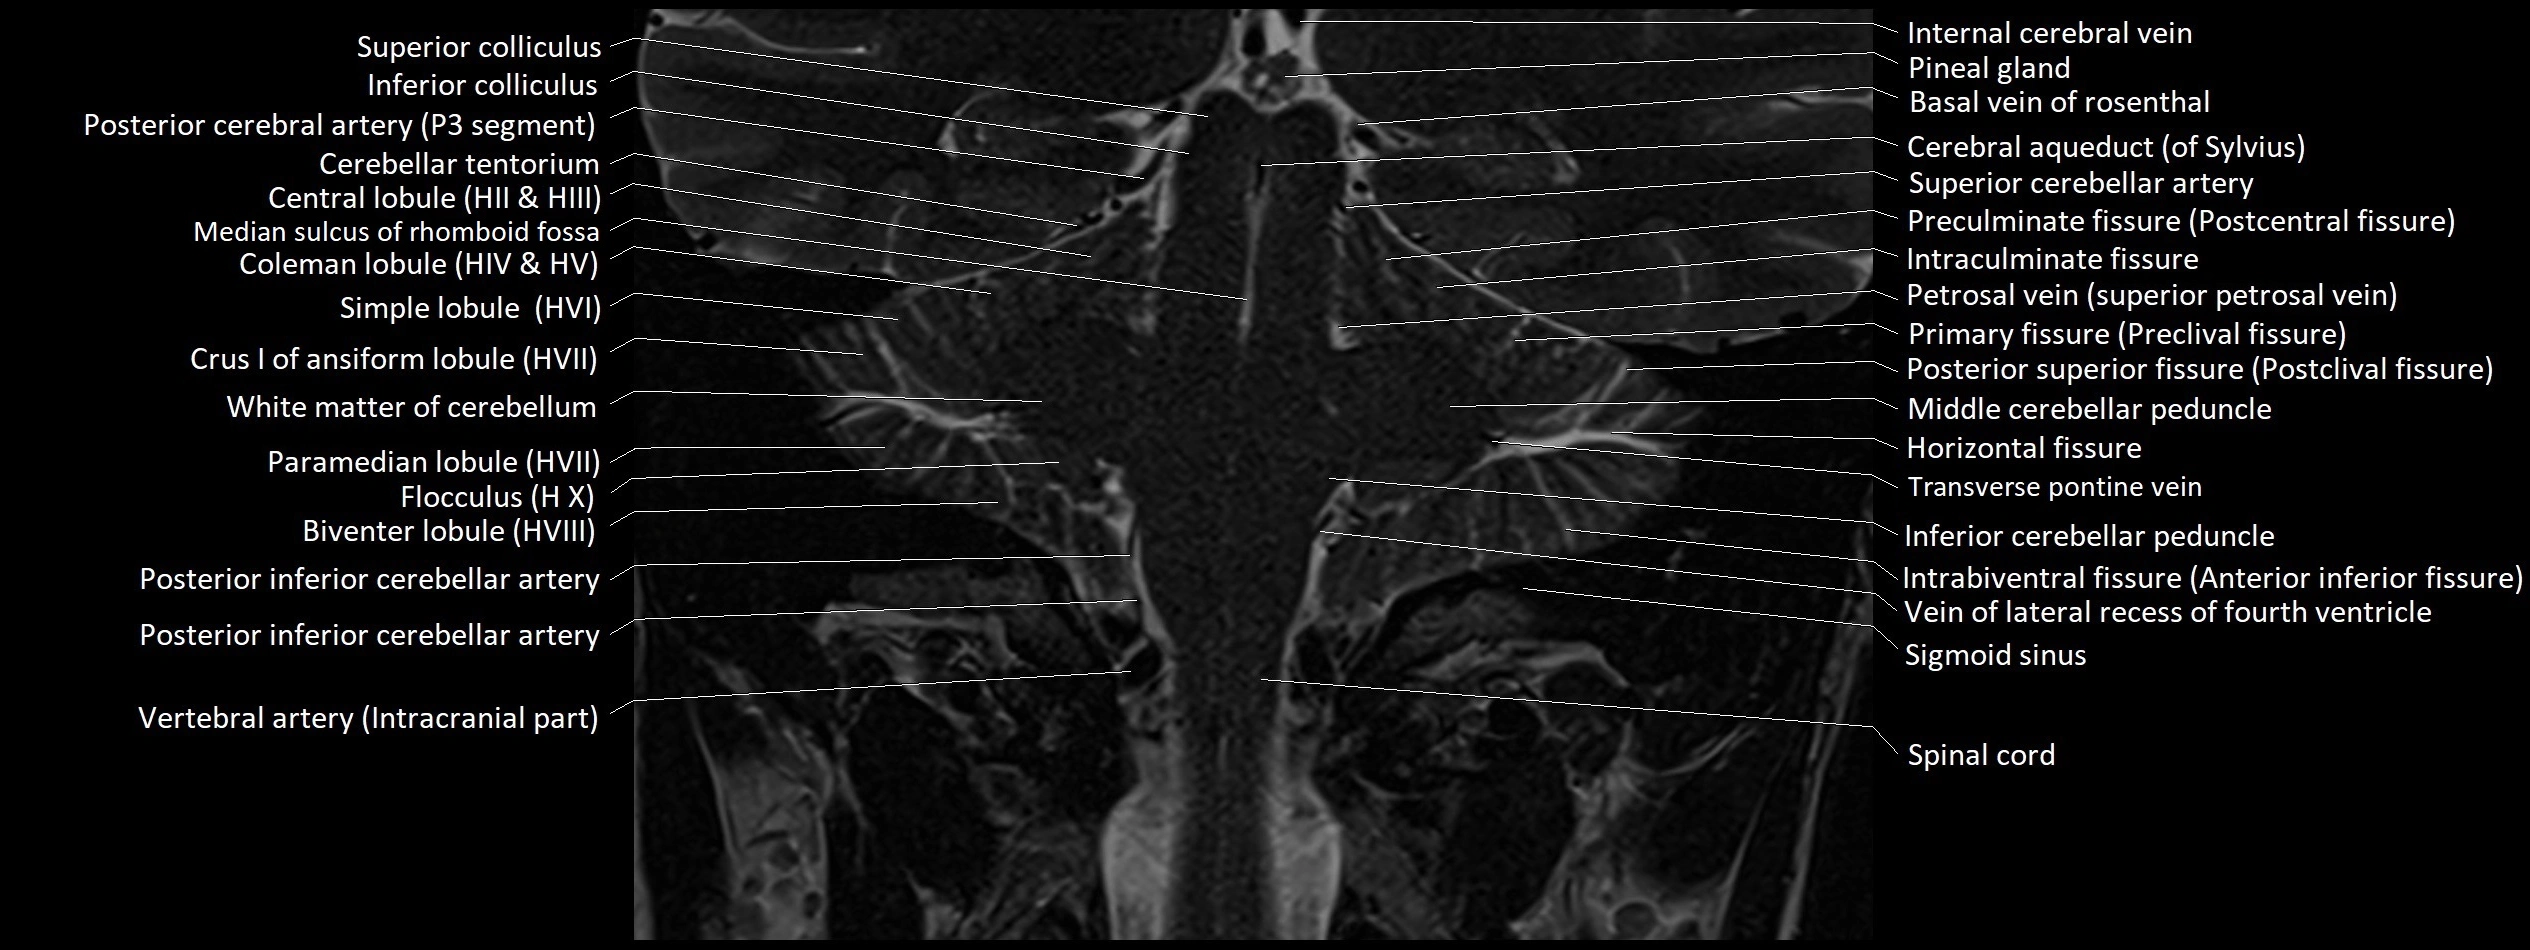

- Central lobule

- Central lobule (II & III) of Cerebellum

- Cerebellar tentorium

- Crus I of ansiform lobule of cerebellum

- Flocculus

- Inferior cerebellar peduncle

- Internal cerebral vein

- Middle cerebellar peduncle

- Paramedian lobule (HVII) of cerebellum

- Peduncle of flocculus

- Petrosal vein

- Pineal gland

- Posterior cerebral artery (P1 Segment)

- Posterior cerebral artery (P3 Segment)

- Posterior inferior cerebellar artery

- Precentral cerebellar vein

- Preculminate fissure

- Primary fissure

- Sigmoid sinus

- Simple lobule (HVI) of cerebellum

- Transverse pontine vein

- Transverse sinus

- Vein of lateral recess of fourth ventricle

- Wing of central lobule